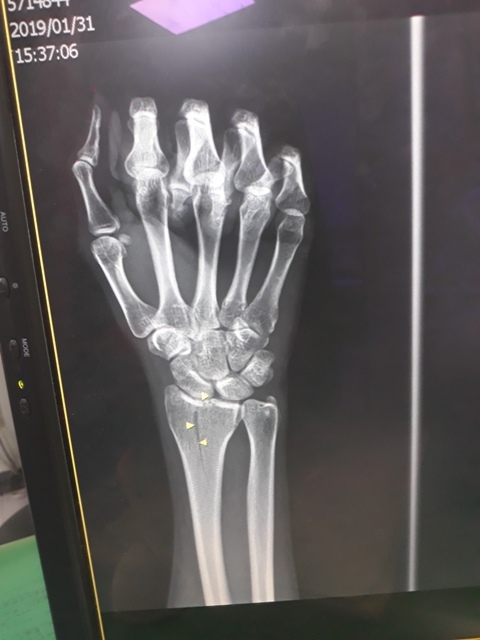

右手X光↓

下午兩點初,爸媽從雲林來到台中,約三點半左右載我去澄清醫院。到達後先照了手和腳各兩張的X光,照完再至門診報到。骨裂後一段時間,當骨頭有感覺比較好時,很期待趕快去回診,想盡快知道我恢復了多少,但到了門診這天,原本應是期待的心情卻也參雜了些許不安的情緒。

進入門診前,我自認為手比腳恢復還快,因為比起一開始,手指比較能出力了,手腕可轉動的範圍也變大了。腳因一直用副木石膏固定住,不能動,所以也不知恢復多少。進入門診後,黃醫師說斷裂的骨頭都沒移位。手沒什麼進展(骨頭不會長那麼快),腳的部份下回再來復診時,可能會恢復的較快了。

手沒什麼進展這件事,讓我比較吃驚,詢問黃醫師,手如果也改用副木,會不會比較好,黃醫師說,他個人是認為沒什麼差。他看著X光片照出來的結果,說開刀或不開刀他覺得都差不多。